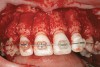

Figure 4a  Corticotomy SFOT. A 42-year-old male presented with a history of extraction orthodontic therapy (A). Incisors were too upright and had severe incisal wear. He was concerned about esthetics of the worn teeth and his insufficient lip support.

Figure 4a

Figure 4b  Progress photo and panorex 9 months after corticotomies were performed on Nos. 6 through 11 (B and C). Previous extraction sites were reopened orthodontically to improve function and fill lip support. Incisal edges were restored provisionally with composite resin. Note that despite the creation of adequate spaces to replace missing teeth, there is inadequate room for placement of dental implants because of severe tipping of all the anterior teeth. Osteotomy SFOT may have been a better choice because it would have allowed needed alveoloskeletal correction (without excessive tipping) instead of the primarily dentoalveolar correction common in corticotomy SFOT. Restorative dentist: Brad Jones, DDS.

Figure 4b

Figure 4c  Progress photo and panorex 9 months after corticotomies were performed on Nos. 6 through 11 (B and C). Previous extraction sites were reopened orthodontically to improve function and fill lip support. Incisal edges were restored provisionally with composite resin. Note that despite the creation of adequate spaces to replace missing teeth, there is inadequate room for placement of dental implants because of severe tipping of all the anterior teeth. Osteotomy SFOT may have been a better choice because it would have allowed needed alveoloskeletal correction (without excessive tipping) instead of the primarily dentoalveolar correction common in corticotomy SFOT. Restorative dentist: Brad Jones, DDS.

Figure 4c